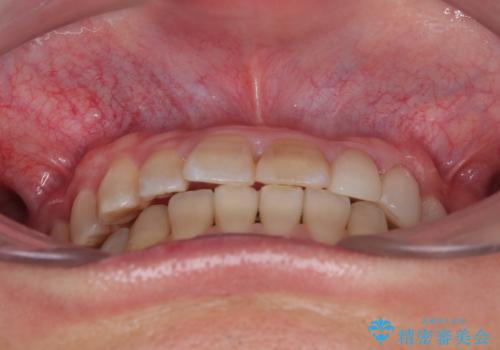

上顎が側方に拡大されて歯が並ぶスペースを確保できました。

それに伴い下顎の歯列も拡大され、舌側に倒れているのが改善されました。